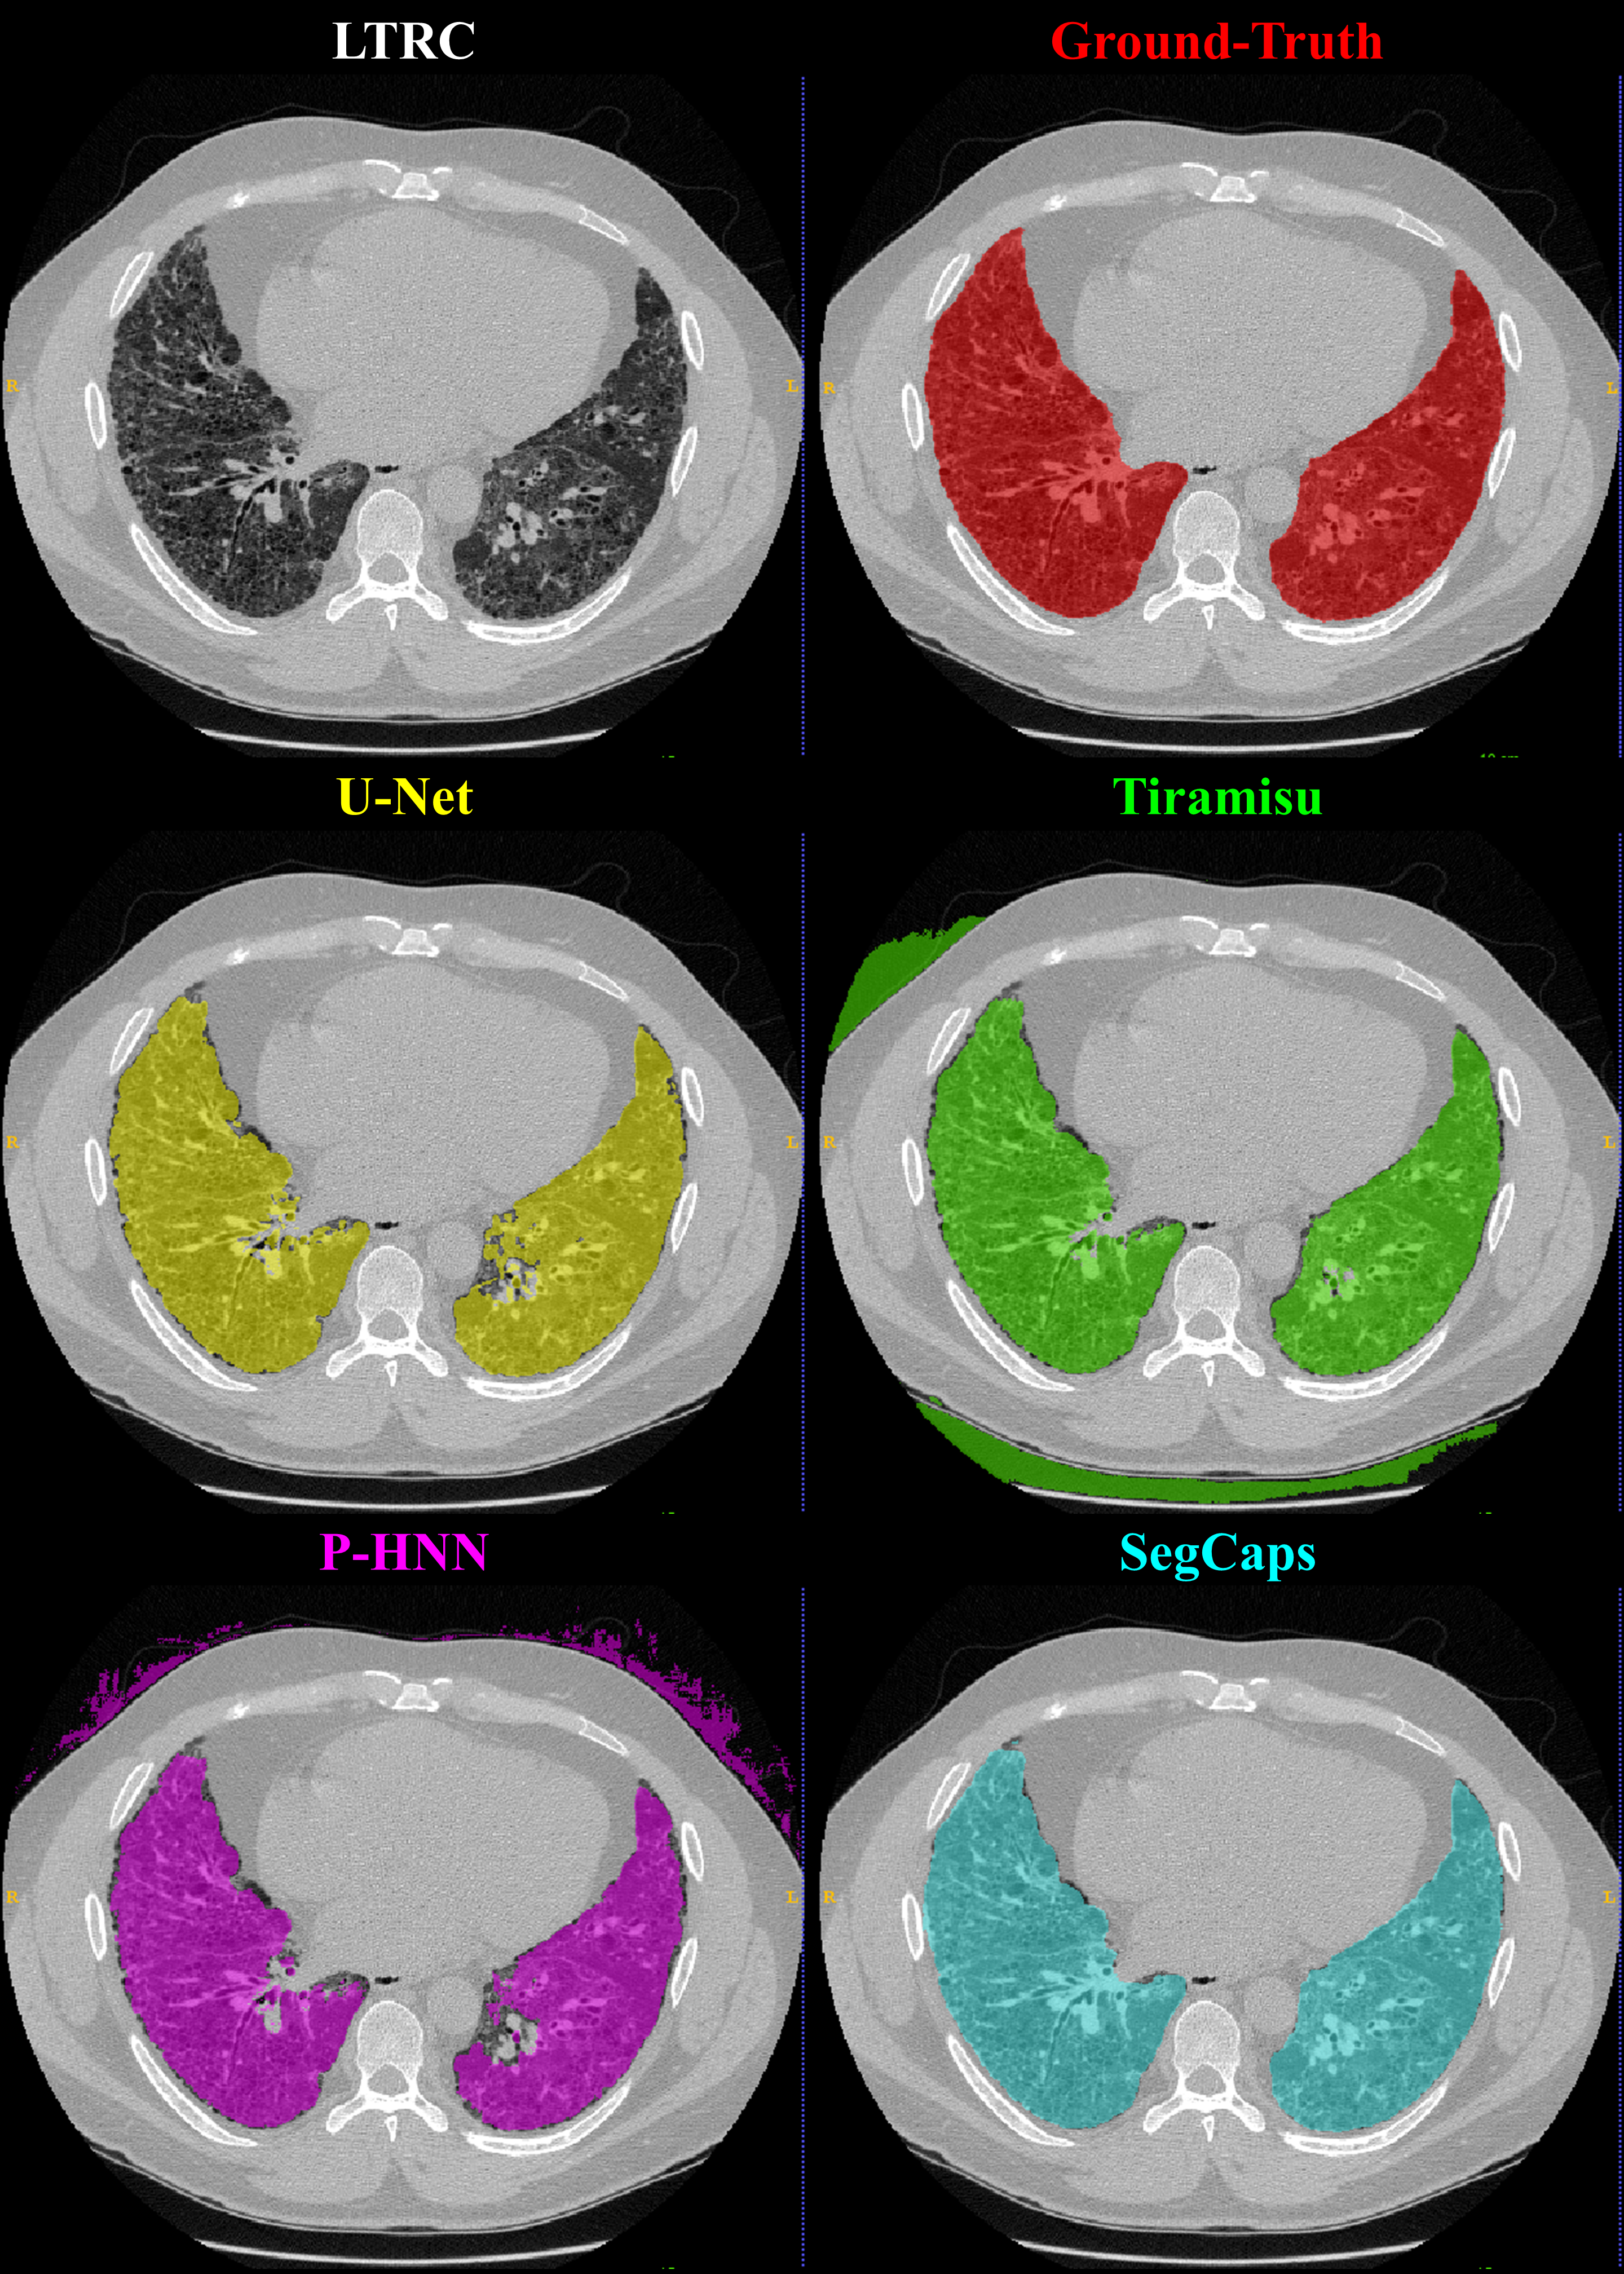

Refer to caption

Fig. 5: Qualitative results for a 2D slice from a CT scan taken from the LTRC dataset. It can be noticed that the CNN-based methods’ typical failure cases are where the pixel intensities (Hounsfield units) are far from the class mean (i.e. high values within the lung regions or low values outside the lung regions).

Qualitative results for typical samples from all datasets are shown in Figure s 4 8. As can be seen in these qualitative examples, SegCaps achieves higher results by not falling into the typical segmentation failure causes, namely over-segmentation and segmentation-leakage. These qualitative examples are supported by our quantitative findings where over-segmentation is best captured by the HD metric and segmentation-leakages are best captured by the Dice metric.